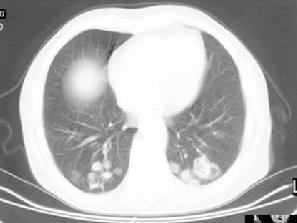

韦格纳肉芽肿(Wegeners granulomatosis,WG)是一种以上、下呼吸道坏死性、肉芽肿性血管炎,肾小球肾炎和其他器官的血管炎为主要特征的全身系统性疾病。病变累及小动脉、静脉及毛细血管。临床上常表现为鼻和鼻窦炎、肺病变及进行性肾功能衰竭。